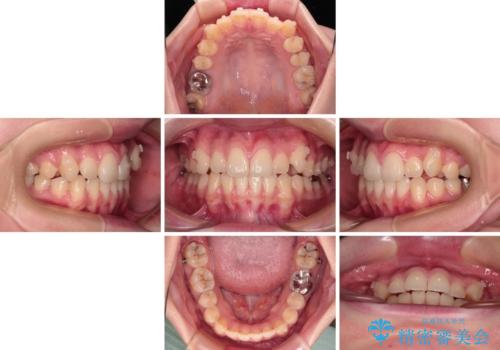

- 左右の八重歯を気にして来院された患者様です。

歯列としてはインビザラインでもワイヤー矯正でも対応できるものでしたが、インビザラインによる治療を希望されていました。

上顎の八重歯改善にインビザラインでは時間のかかってしまう可能性があり、更には口元が治療前よりも突出してしまう可能性があったため、補助装置により八重歯を事前に引き込んでおくことで、インビザラインによる治療をスムーズに行えるように計画しました。